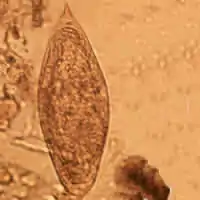

| Schistosoma mansoni egg | |

Adult flatworms parasitize blood capillaries of either the mesenteries or plexus of the bladder, depending on the infecting species. They are unique among trematodes and any other flatworms in that they are dioecious with distinct sexual dimorphism between male and female. Thousands of eggs are released and reach either the bladder or the intestine (according to the infecting species), and these are then excreted in urine or feces to fresh water. Larvae must then pass through an intermediate snail host, before the next larval stage of the parasite emerges that can infect a new mammalian host by directly penetrating the skin.

Thirteen species are found in Africa. Twelve of these are divided into two groups—those with a lateral spine on the egg (mansoni group) and those with a terminal spine (haematobium group).

Comparison of eggs